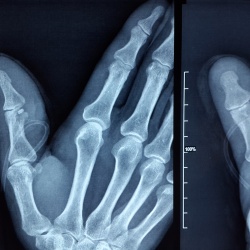

Женщина лет 50-ти. Появились неприятные ощущения в большом пальце правой руки, слабовыраженная болезненность. В районной больнице сделали снимок, предположили, инородное тело (как оно могло...